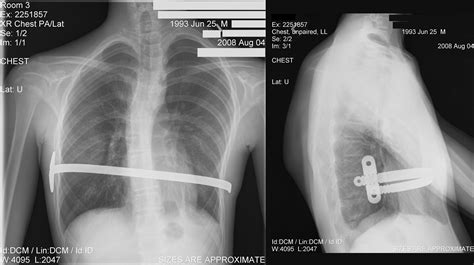

• Follow-Up Visits: Regular follow-up visits with the surgeon are essential to monitor the progress of the correction and ensure the bar is in the correct position.

• Bar Removal: The metal bar is typically left in place for 2 to 4 years, allowing the chest to grow and maintain its corrected shape. Once the chest has stabilized, the bar is removed in a separate outpatient procedure.

During the recovery period, patients may experience some discomfort and pain, which can be managed with medication. It is important to follow the surgeon's instructions carefully to ensure a smooth recovery.